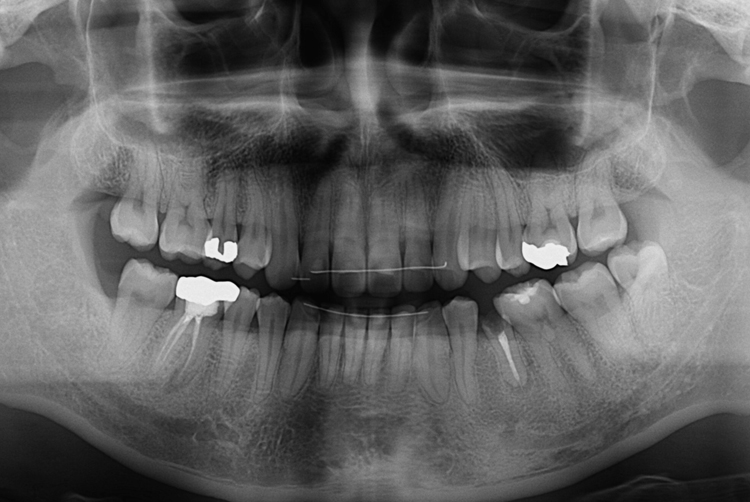

[임플란트] 어금니 임플란트

치료후 : 2018-07-31

세종치과는 많은 환자와 다양한 케이스를 바탕으로

항상 편안한 임플란트 수술을 제공하고자 노력하고,

오래동안 튼튼히 쓸 수 있는 임플란트 수술을 가장 큰 목표로 삼고 있습니다.